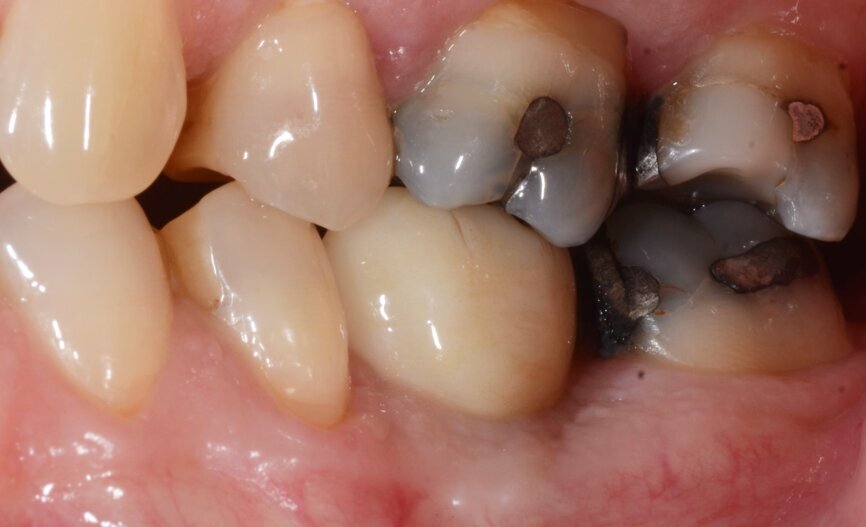

The patient, a 67-year-old non-smoking man without any relevant medical history, was referred to the office with a missing tooth (#36) due to persistent apical periodontitis. The tooth had been extracted more than one year prior to the procedure and the molar site was well maintained and fully healed (Fig. 1). A CBCT scan showed that the patient had favourable bone availability (Fig. 2), on which basis a one-stage placement of a 5.5 × 10.0 mm Straumann BLX implant was planned. After surgically installing the implant (Figs. 3–7), Salvesen allowed the surrounding soft tissue to mature and heal for six weeks (Fig. 8). He then removed the healing abutment to begin the prosthetic procedures for a temporary crown (Figs. 9 & 10). A stone master cast was made in the laboratory, and a temporary screw-retained PMMA crown was manufactured over a Straumann wide base temporary abutment for the crown (Fig. 11) and placed on to the implant (Figs. 12–14).

Fig. 20: One-year follow-up occlusal view.

Fig. 21: One-year follow-up lateral view.

One year after the treatment, the patient reports complete satisfaction with both his chewing function and the overall aesthetics (Figs. 20 & 21). Radiographs confirm that the molar site is stable and healthy (Fig. 22). In this first human case, use of the Straumann BLX wide base implant delivered efficient and reliable performance, even in soft bone with early loading conditions.